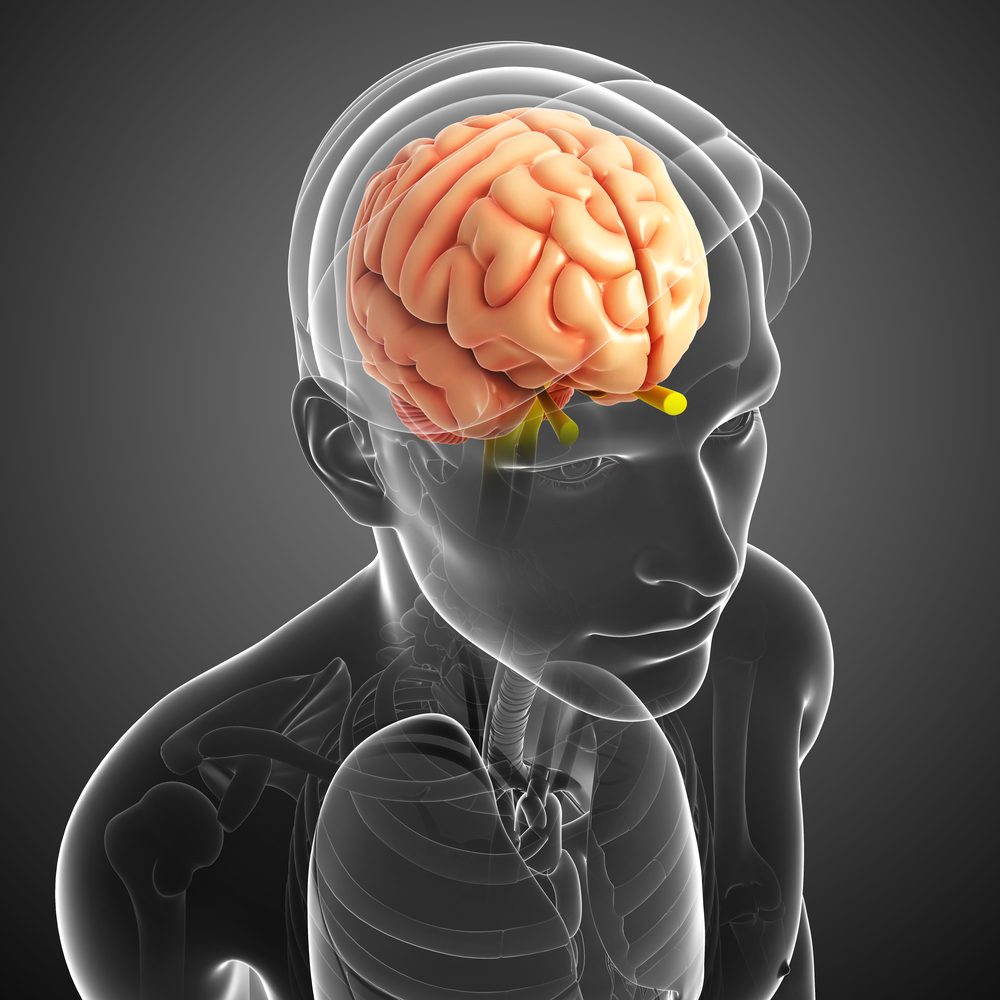

(San Francisco, CA) The University of California, San Francisco announced that it has entered into an exclusive license agreement with Accurexa, Inc for global licensing of a medical stereotactic device.

(San Francisco, CA) The University of California, San Francisco announced that it has entered into an exclusive license agreement with Accurexa, Inc for global licensing of a medical stereotactic device.